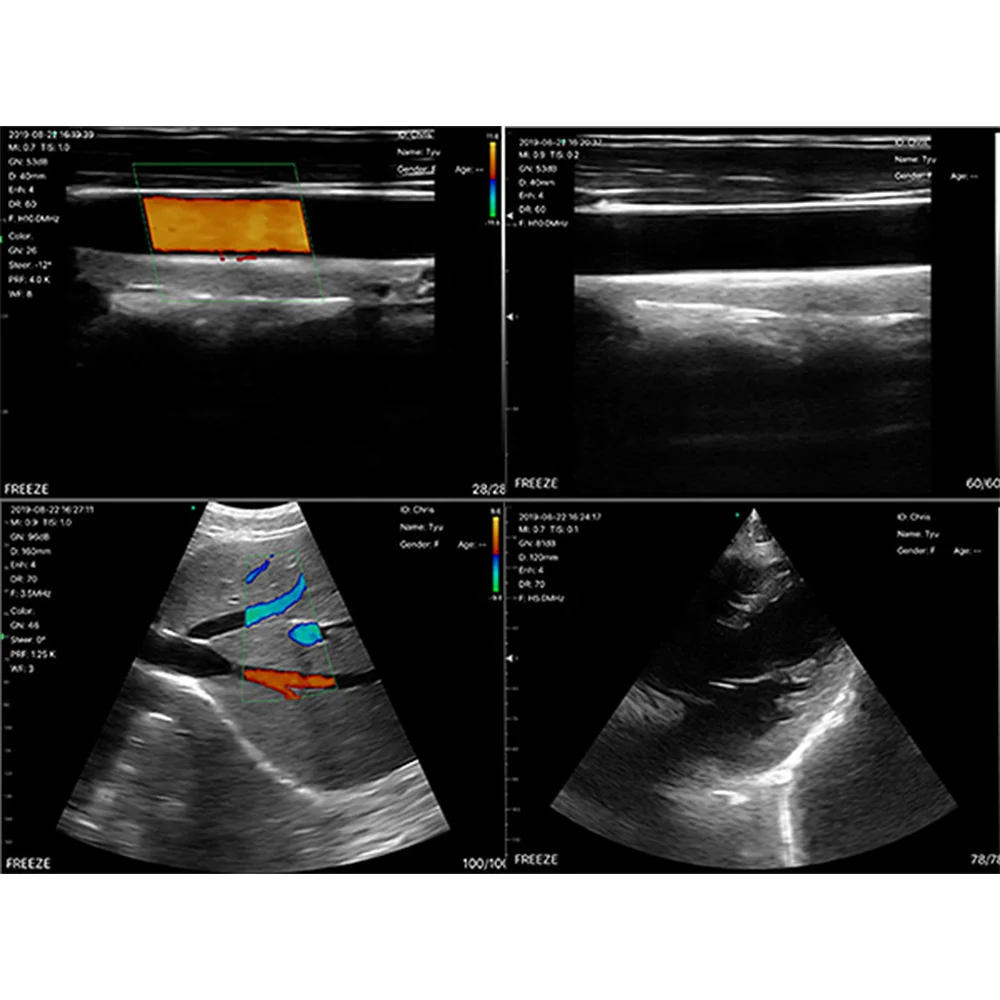

The 3-in-1 Handheld Portable Ultrasound Scanner is a versatile, lightweight diagnostic tool designed for use with Android, iOS, and Windows devices. This compact and wireless device offers high-quality imaging with Color Doppler, making it perfect for a wide range of medical applications. The scanner includes three probe types: convex, linear, and cardiac, providing flexibility for different types of examinations. It supports multiple scanning modes, including B, B/M, Color, PW, and CW, to deliver detailed, real-time images.

- Multiple Scanning Modes: Includes B, B/M, Color, PW, and CW modes for comprehensive diagnostic capabilities.